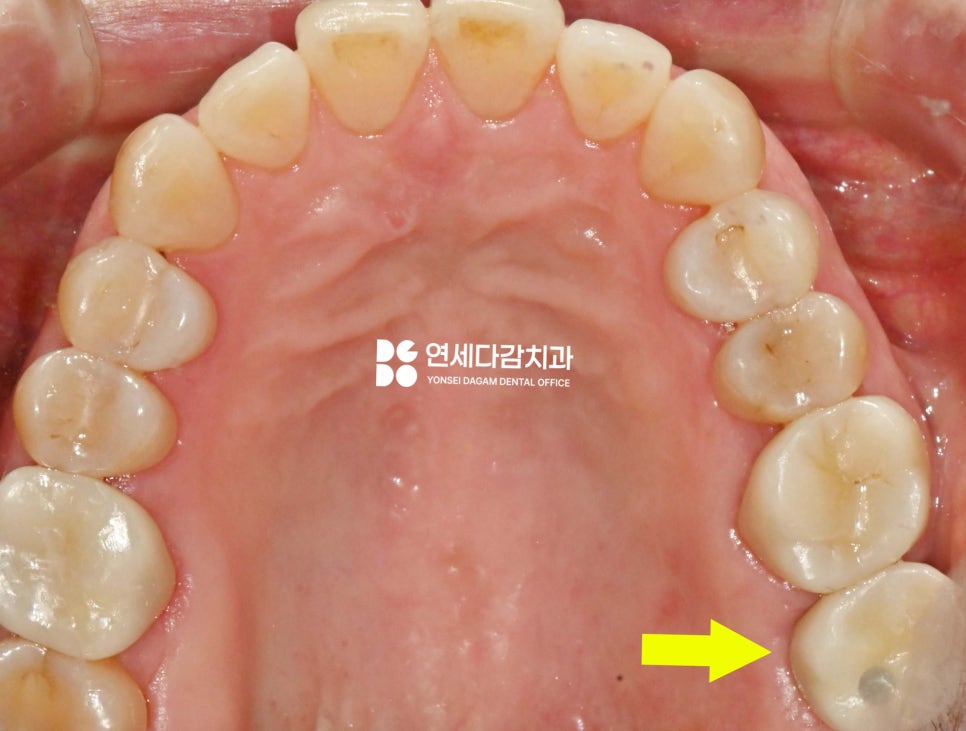

4개월 정도 충분한 치유가 이루어진 후,

임플란트 고정체를 식립했습니다.

기존에 많은 양이 소실된

치조골 높이를 회복시키는 데는

한계가 있기 때문에,

송파역 치과 에서는 안정된 부위를 찾아

다소 깊게 식립할 수밖에 없었습니다.

그러나 이것이 문제가 되는 것은 아닙니다.

이런 경우에는 환자의 구강 상태에 맞춘

맞춤형 임플란트 보철물을 제작하여

안정적으로 완성될 수 있습니다.